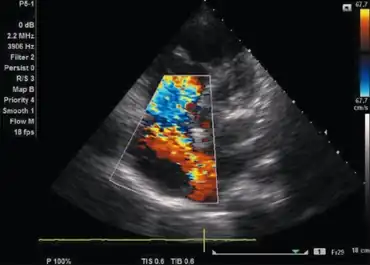

Color flow mapping and Doppler imaging

A color flow and doppler imaging is used to help confirm the presence as well as evaluate the severity of ASD and MS.[9]